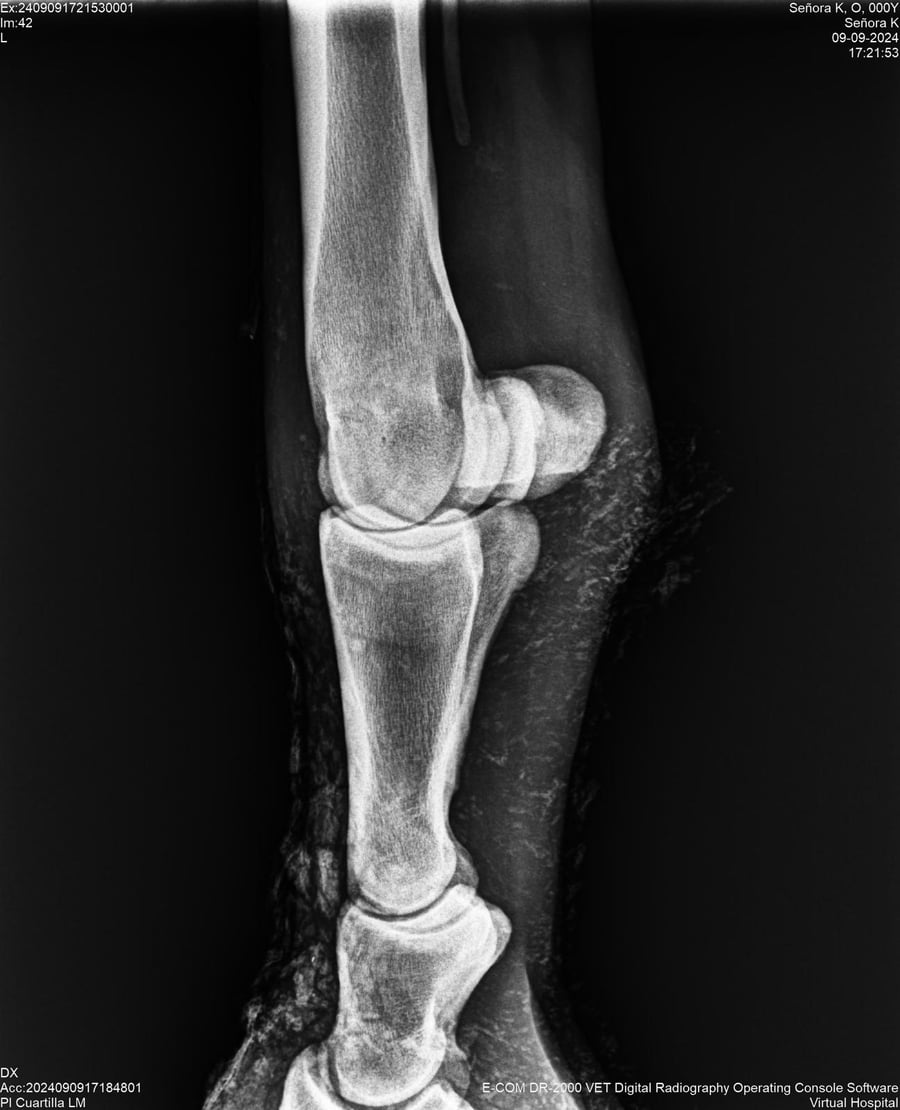

LOTE 44, SEÑORA K

Identificador: #291147-

Generacion 2022